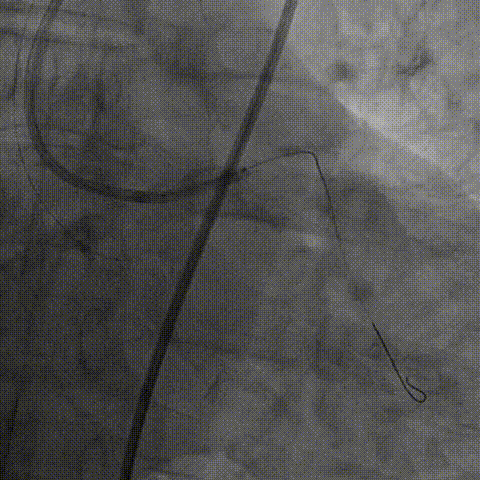

右冠造影,提示右冠近端完全闭塞

正向选择2.5 OTW球囊,Pilot200尝试开通

选择平行导丝:KDL+Pilot200、Gaia3、CP12、8-20

尝试逆向:150 Finecross+SionBlack、Suoh 03

再转正向:Corsair+XT Knucle

再转正向:CP 12、Pilot 200

再转正向:Pilot 200